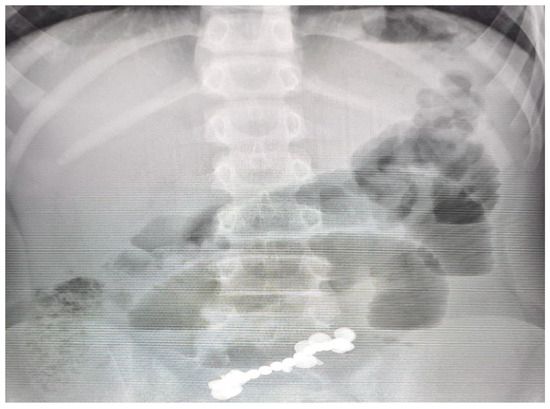

| Day 5 | Abdominal X-ray: clustered radiopaque bodies in distal ileum; no free air |

| Day 5 | Emergency laparotomy: entero-enteric fistula (10 mm), resection of 18 cm ileum, side-to-side anastomosis, retrieval of 13 magnets |